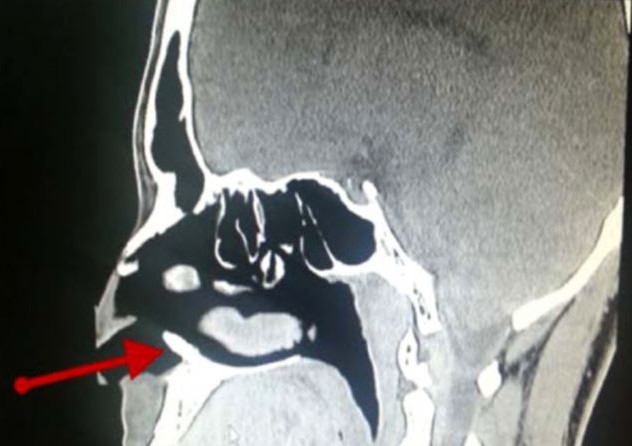

ΦΩΤΟ-«Φύτρωσε» δόντι στη μύτη του

Δεν πίστευαν στα μάτια τους οι γιατροί στη Σαουδική Αραβία όταν είδαν στη μύτη ενός 22χρονου να έχει φυτρώσει ένα δόντι.

Ο 22χρονος τουλάχιστον μία φορά κάθε μήνα τα τελευταία τρία χρόνια αιμορραγούσε από τη μύτη, αλλά ποτέ δεν έδωσε ιδιαίτερη σημασία και άφηνε το φαινόμενο να συνεχίζεται.

Όταν, πλέον, αποφάσισε να επισκεφθεί τον γιατρό έμεινε με το στόμα ανοιχτό. Ένα δόντι είχε φυτρώσει και μεγάλωνε καθημερινά με αποτέλεσμα να «τρώει» το δέρμα και να προκαλεί την αιμορραγία.

Τελικά ο 22χρονος υπεβλήθη σε επέμβαση και το πρόβλημά του λύθηκε. Έχασε, βέβαια, ένα δόντι…